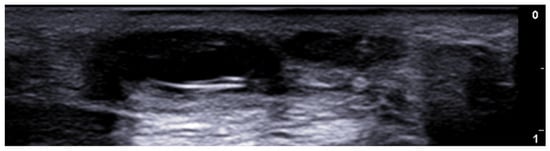

5. Specific Cutaneous Structure and Sites of Skin Disorders